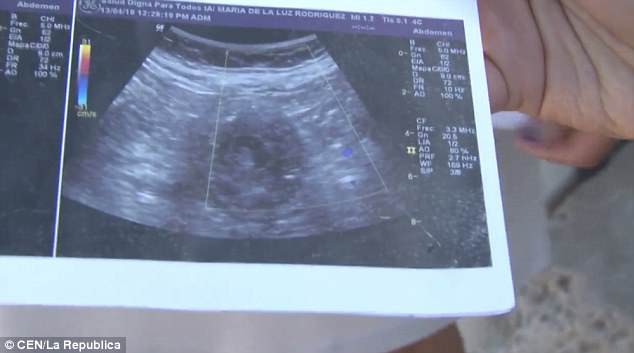

70歲的墨西哥婦人Maria de la Luz聲稱自己現懷有6個月身孕,並展示超聲波掃描照片,表示她確實懷有一名女嬰。倘若屬實,Maria de la Luz將成為全世界最年長的孕婦,比現有紀錄保持者年長4年。

Maria de la Luz說:「當時我嘔吐、頭暈和腳痛,在私人診所和公立醫院前後做了10次左右的超聲波掃描,醫生亦不敢相信我懷孕。」